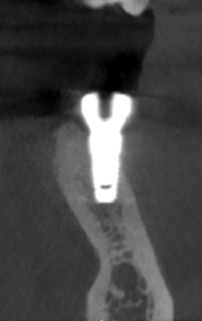

Установка имплантата

Установка имплантата по хирургическому шаблону осуществляется в строго запланированное место. Безопасно. Никаких разрезов, просто прокол в десне

Более 90% осложнений при имплантации никак не связаны с имплантационной системой, а зависят от точности установки имплантата. Любой имплантат должен быть установлен на определенный угол и глубину и чем точнее это сделано, тем меньше проблем будет у пациента. Любой перекос имплантата может вызвать осложнения. Сравните сами. При классической имплантации точность установки имплантата составляет не более 3 мм. Имплантация с шаблоном позволяет установить имплантат с точностью 10 микрон, что в 300 раз точнее, а значит в 300 раз безопаснее.

Примеры работ по имплантации по шаблону без разрезов и швов